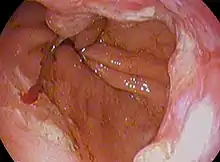

Endoscopic image of an esophageal adenocarcinoma

Although an occlusive tumor may be suspected on a barium swallow or barium meal, the diagnosis is best made with an examination using an endoscope. This involves the passing of a flexible tube with a light and camera down the esophagus and examining the wall, and is called an esophagogastroduodenoscopy. Biopsies taken of suspicious lesions are then examined histologically for signs of malignancy.